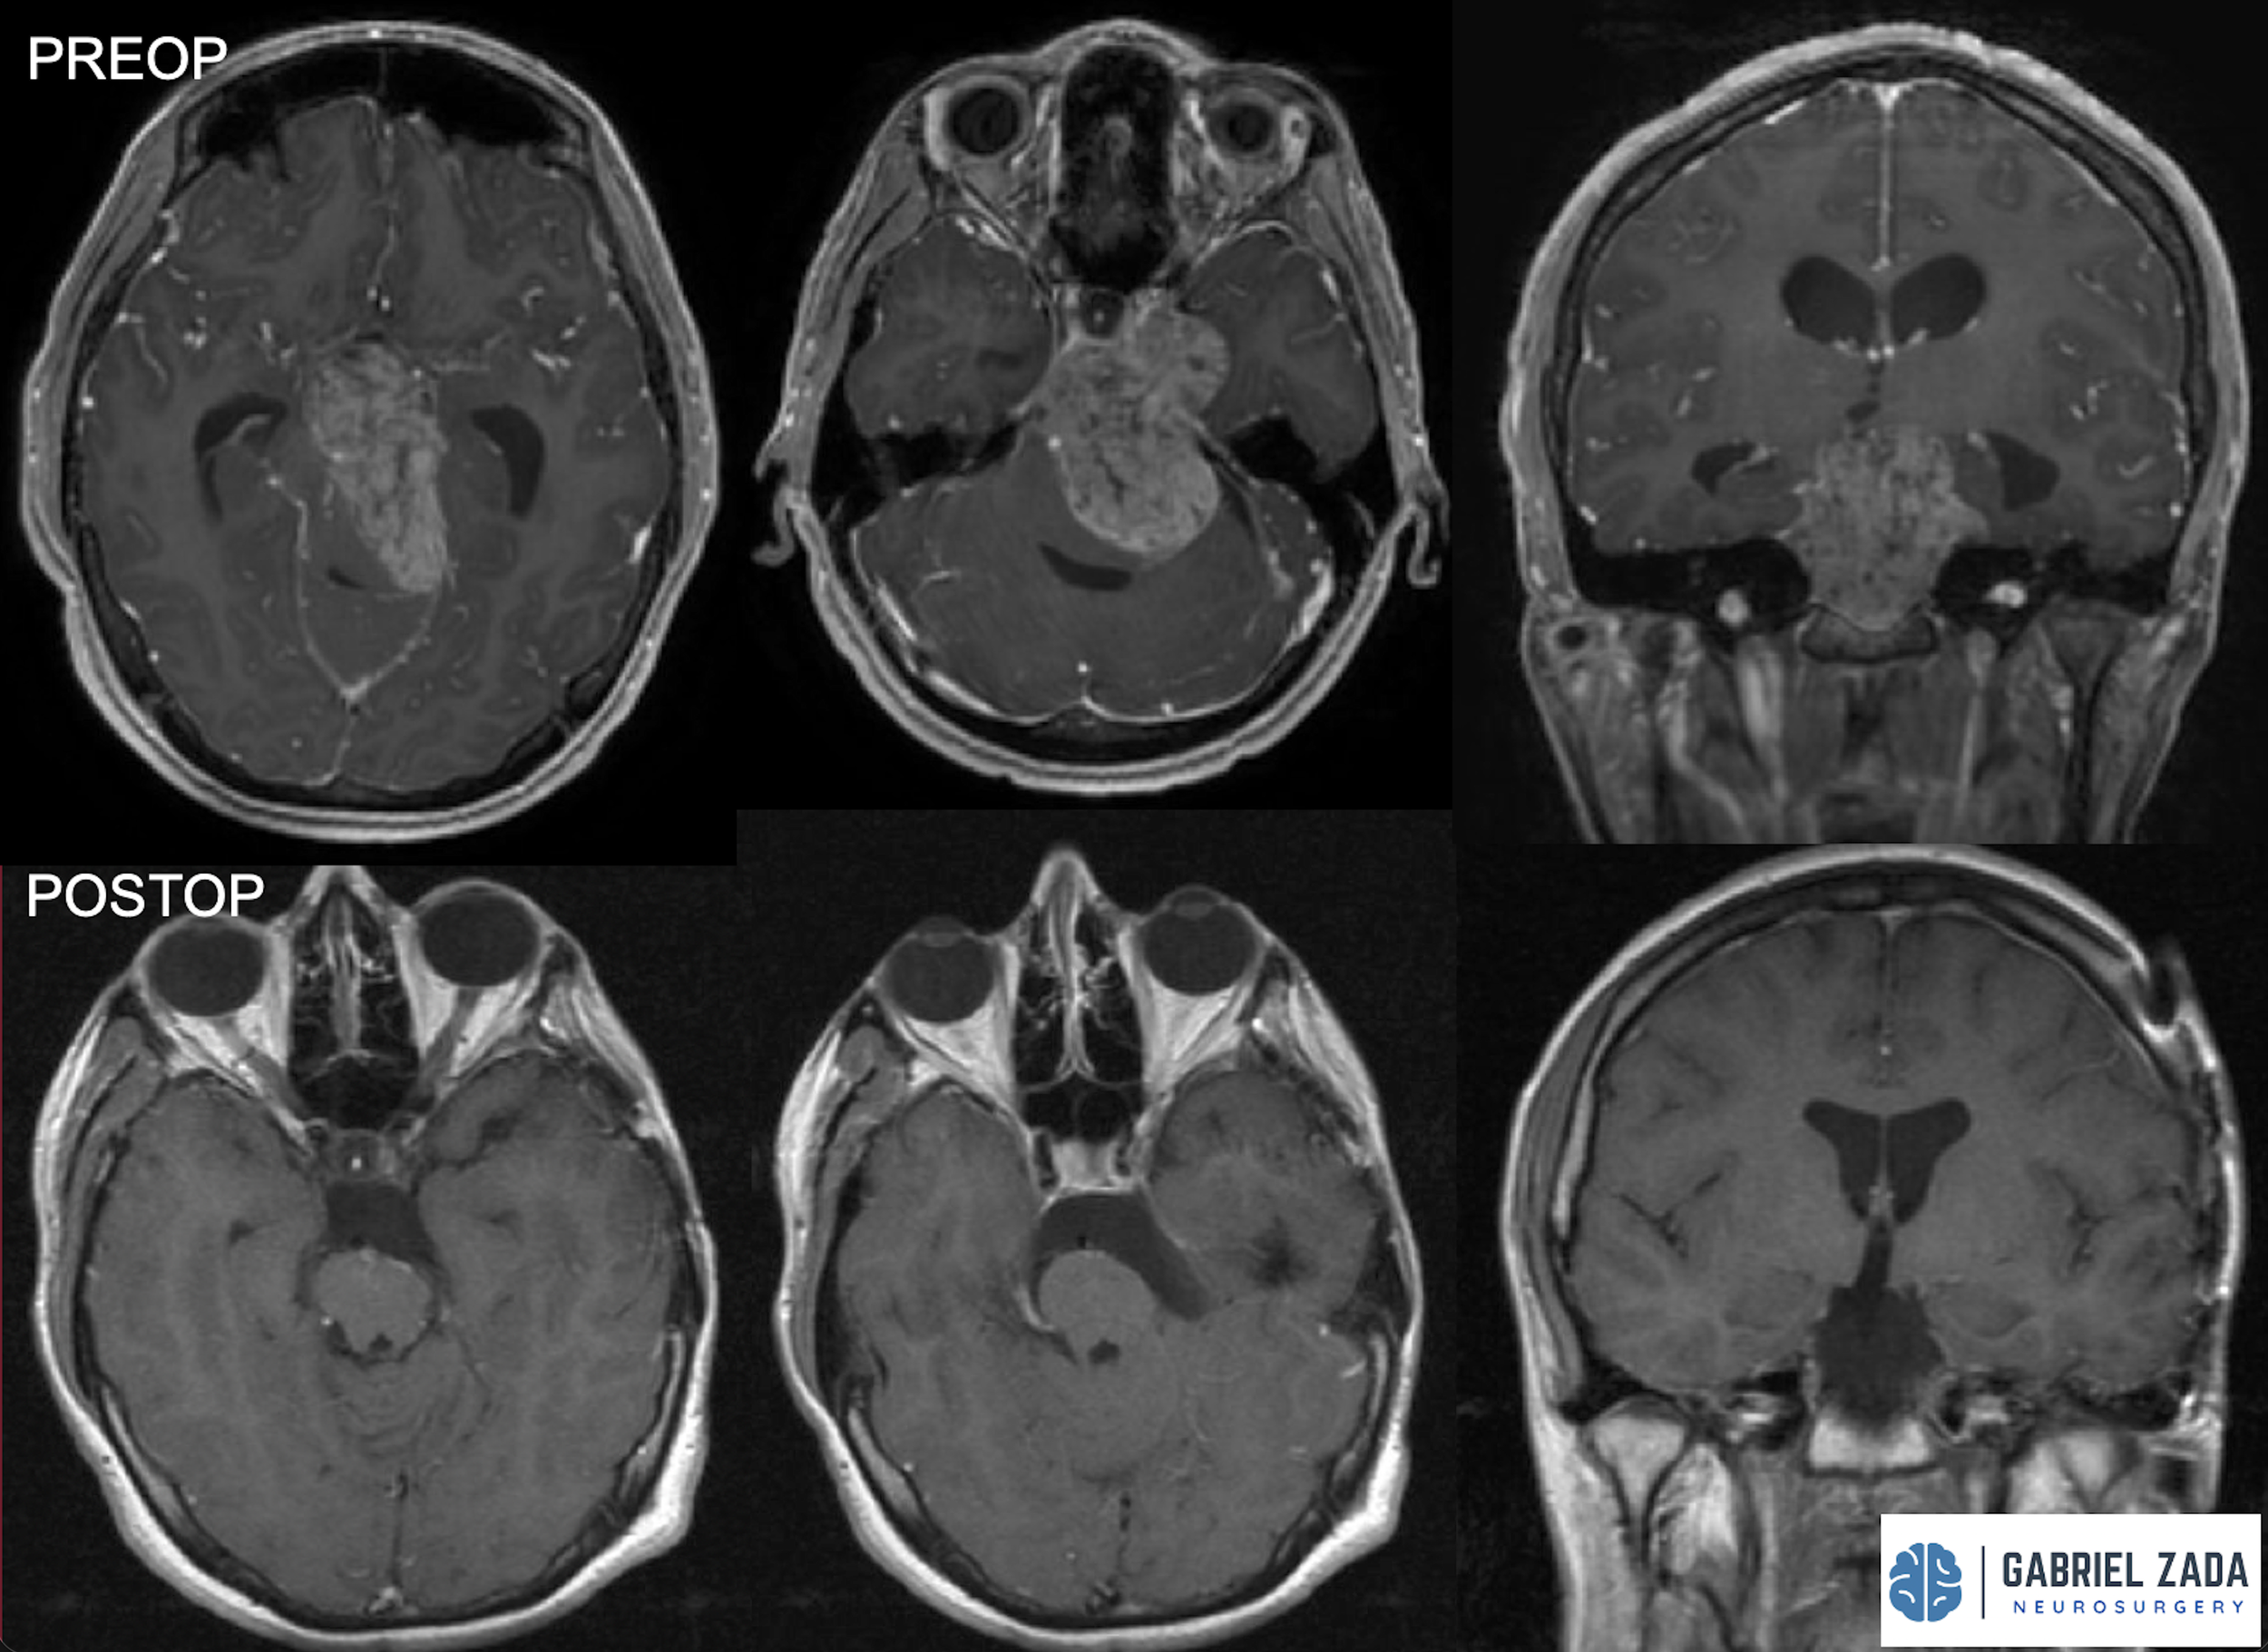

Explore this comprehensive gallery featuring pre‑ and post‑operative imaging of patients with skull‑base tumors treated by Gabriel Zada, MD, MS, FAANS, FACS. These cases highlight Dr. Zada’s expertise in advanced neurosurgical techniques and outcomes.

*Representative cases shown for educational purposes. All images de-identified. Individual results vary.